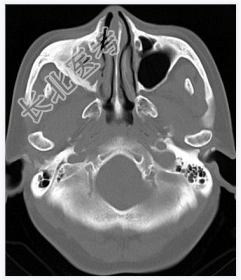

- [材料题] 女性,50岁。鼻塞2年余,有异物感,有血性分泌物,伴面颊疼痛。行CT检查。

- 简答题1、患者的诊断及依据是什么?

- 简答题2、需要与哪些疾病鉴别?